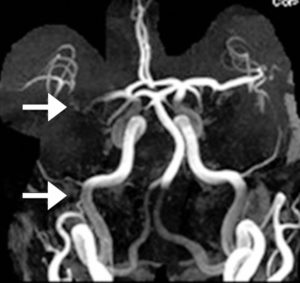

- 緊急磁力共振MRI造影對於在中風黃金小時內進行準確診斷至關重要,尤其是對於缺血性中風。

- MRI 可提供腦部及其血管的詳細影像,從而評估中風類型。

- MRI 亦可顯示缺血性中風時血管阻塞的部位和範圍,或出血性中風時出血的部位和範圍,從而提供選擇合適治療方案的指導。